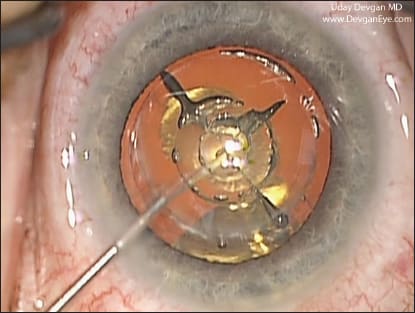

COURTESY: GITANE PATEL, MD, M.P.H. AND JAY S. PEPOSE, MD, PH.D.

Figure 2. A patient one day following LASIK presented with pain, decreased vision and focal clustered infiltrates, some extending beyond the flap margin. These are warning signs of early LASIK-associated microbial keratitis, requiring flap lift, culture and scraping, antibiotic irrigation of the interface and intensive antibiotic treatment.